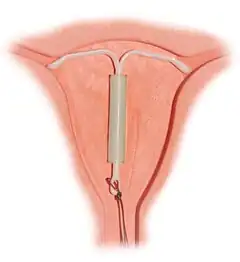

Correctly inserted IUD | |

The hormonal IUD is a small T-shaped piece of plastic, which contains levonorgestrel, a type of progestin.[23] The cylinder of the device is coated with a membrane that regulates the release of the drug.[69] Bayer markets Skyla as Jaydess in the United Kingdom.[70] Jaydess releases six micrograms per day and lasts for three years.[71] In comparison, oral contraceptives can contain 150 micrograms of levonorgestrel.[45] The hormonal IUD releases the levonorgestrel directly into the uterus, as such its effects are mostly paracrine rather than systemic. Most of the drug stays inside the uterus, and only a small amount is absorbed into the rest of the body.[45]

Insertion

During the insertion, the vagina is held open with a speculum, the same device used during a pap smear.[45] A grasping instrument is used to steady the cervix, the length of the uterus is measured for proper insertion with a uterine sound for decreasing chance of uterine perforation with the IUD, and the IUD is placed using a narrow tube through the opening of the cervix into the uterus.[45] A short length of monofilament plastic/nylon string hangs down from the cervix into the vagina. The string allows physicians and patients to check to ensure the IUD is still in place and enables easy removal of the device.[45] Moderate to severe cramping can occur during the procedure, which generally takes five minutes or less. Insertion can be performed immediately postpartum and post-abortion if no infection has occurred.[18]